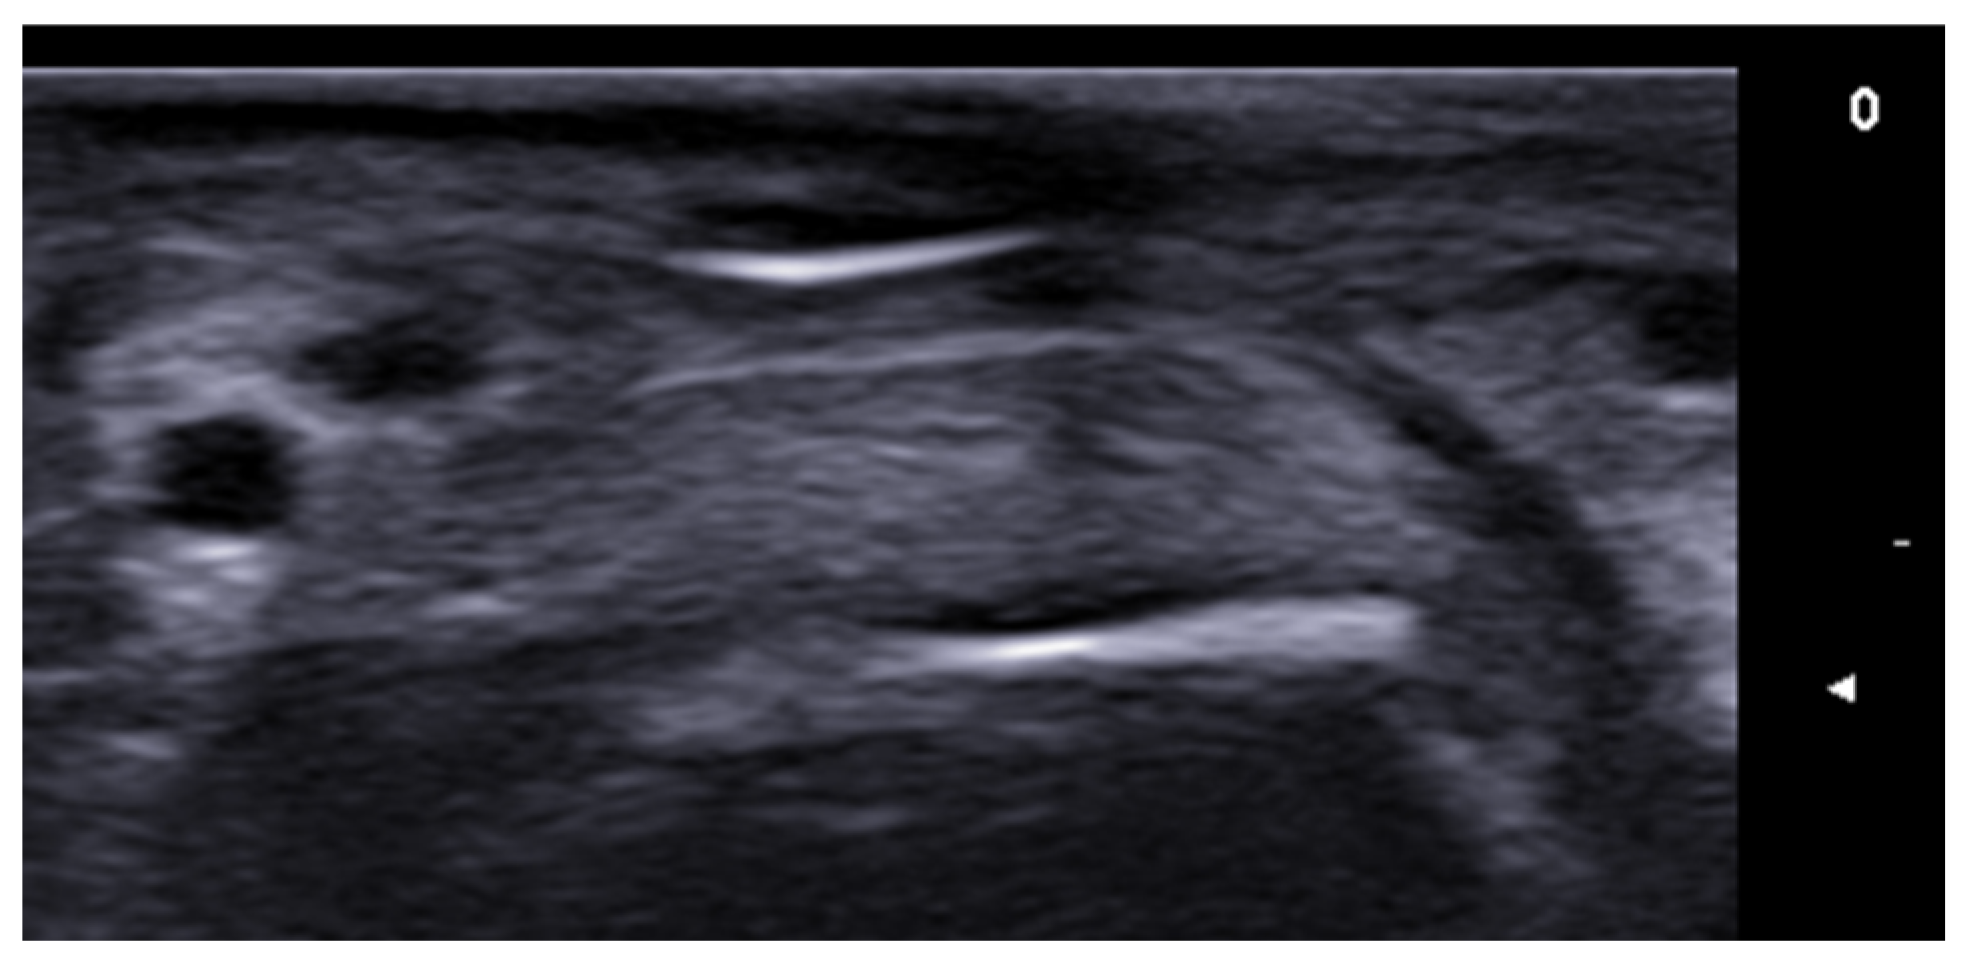

- Di Battista, M.; Vitali, S.; Barsotti, S.; Granieri, G.; Aringhieri, G.; Morganti, R.; Dini, V.; Della Rossa, A.; Romanelli, M.; Neri, E.; et al. Ultra-high frequency ultrasound for digital arteries: Improving the characterization of vasculopathy in systemic sclerosis. Semin. Arthritis Rheum. 2022, 57, 152105. [Google Scholar] [CrossRef] [PubMed]